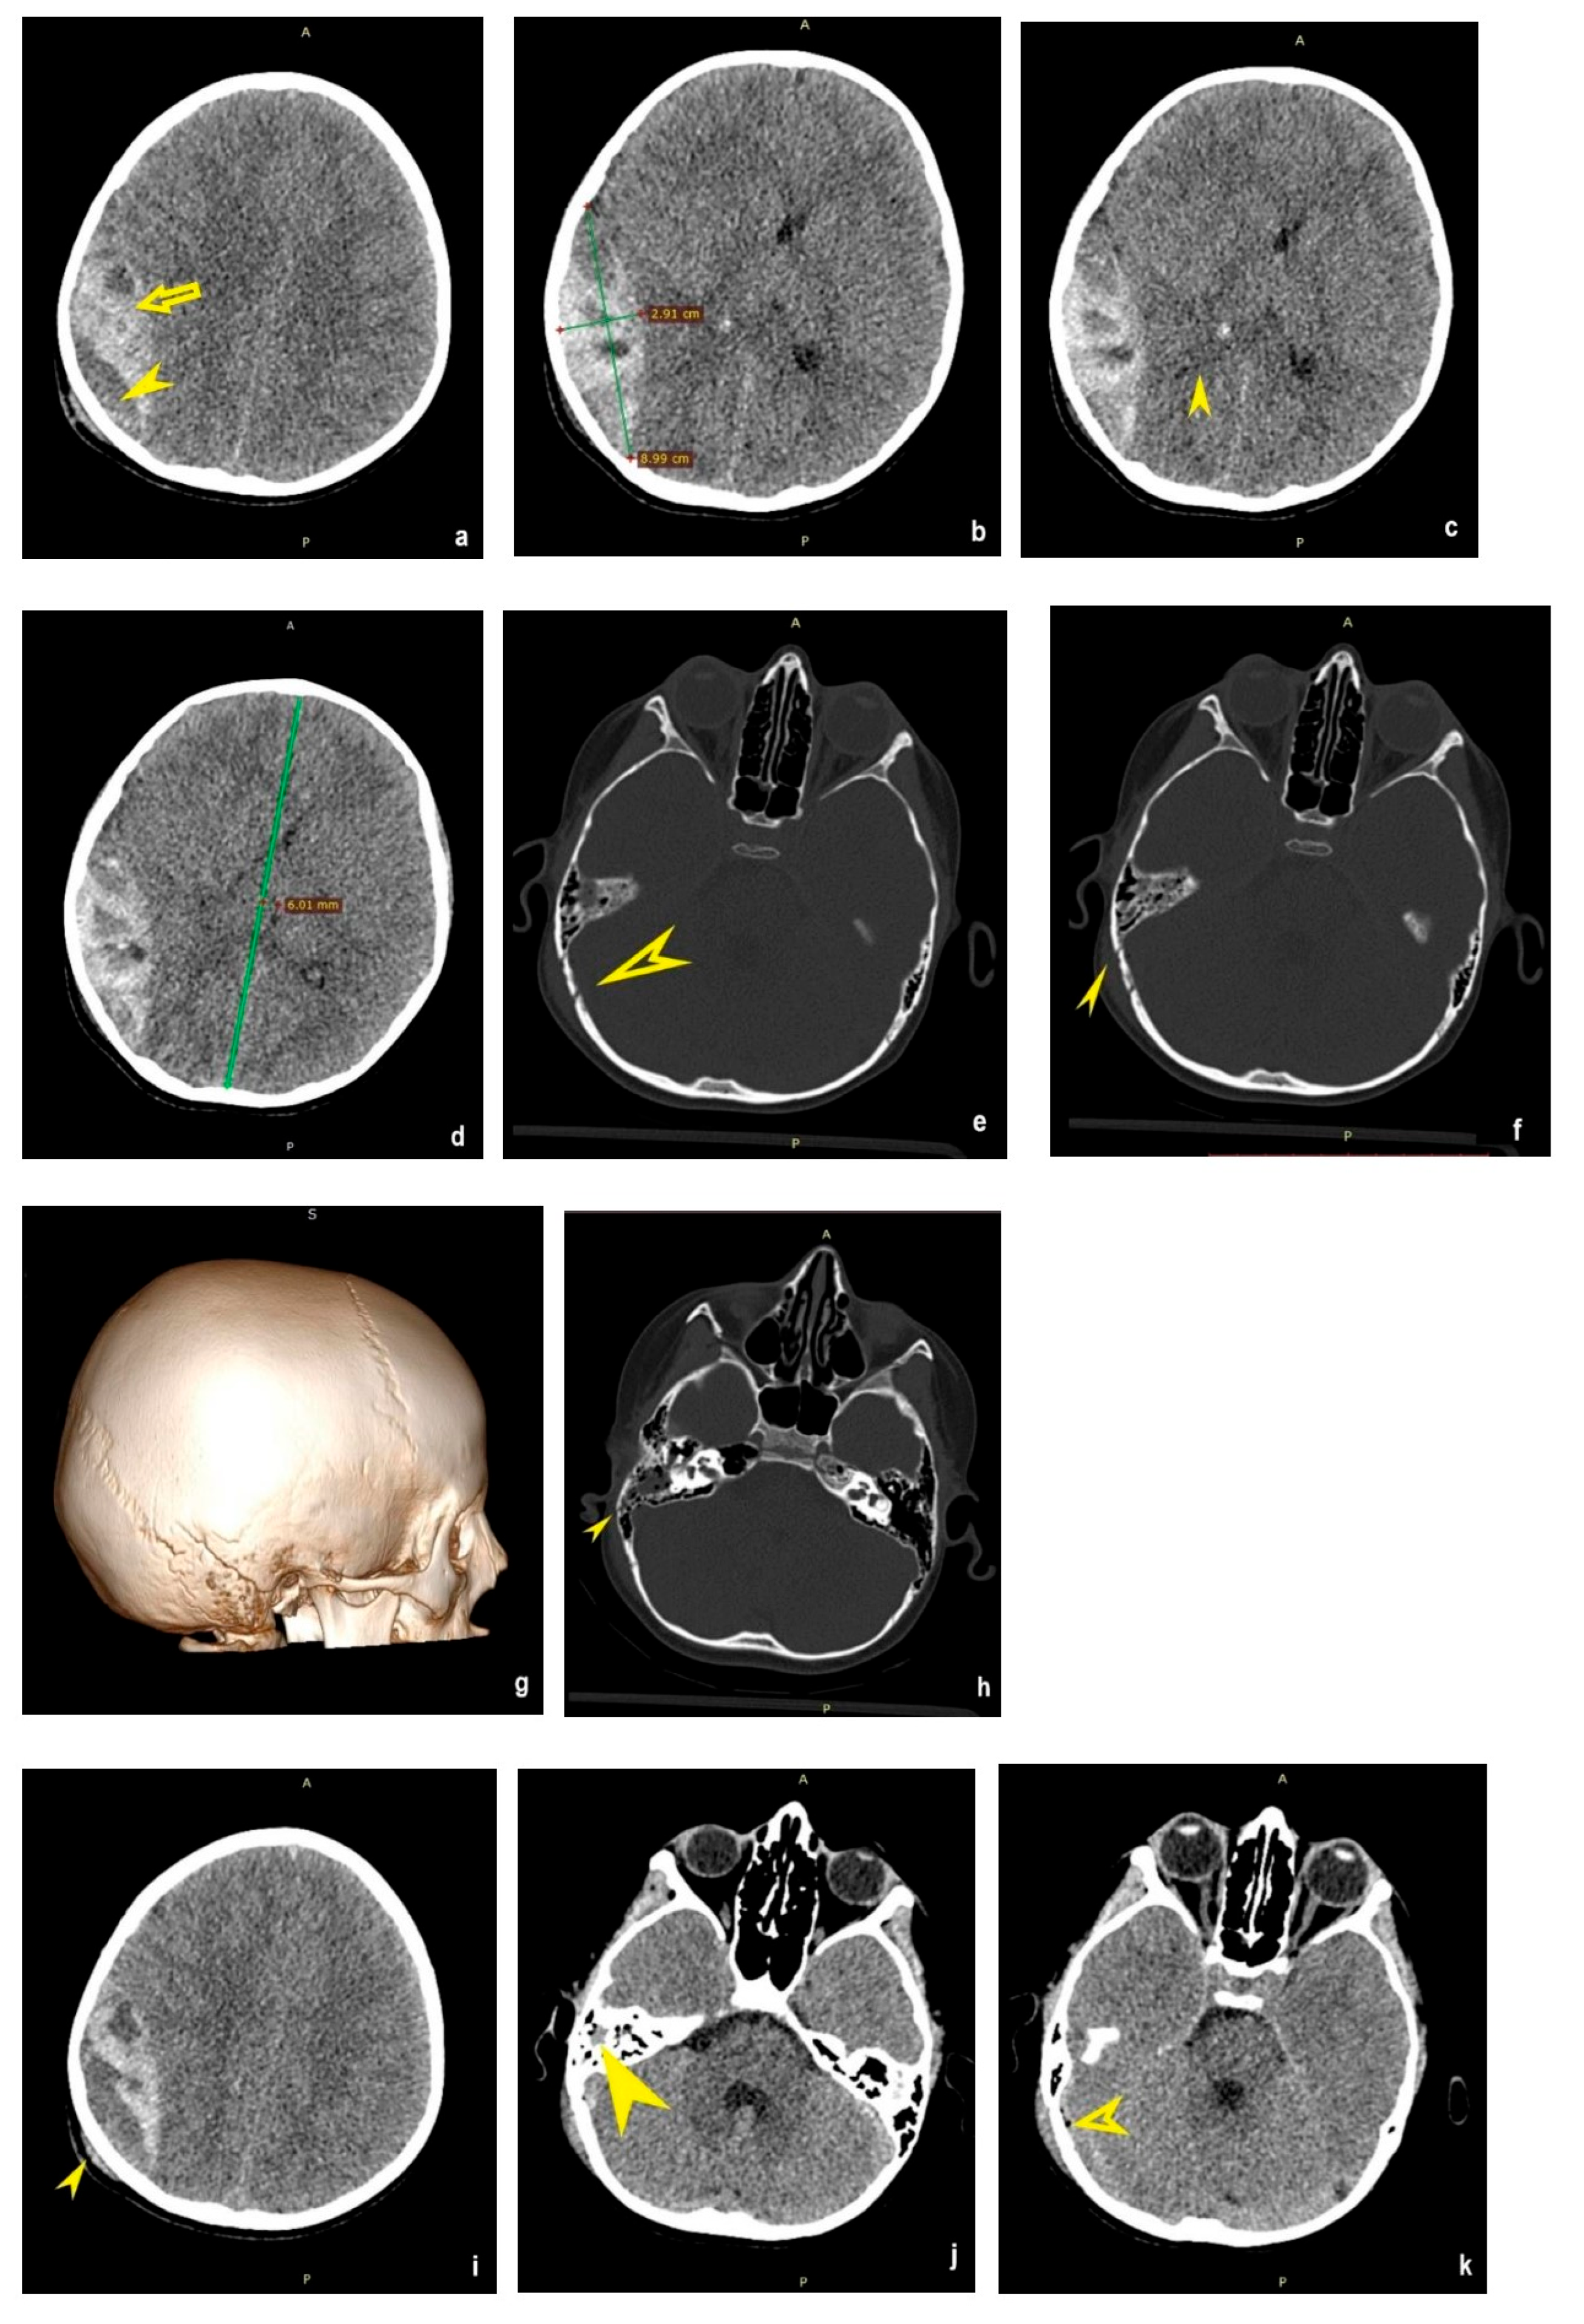

2.1. First Case Report